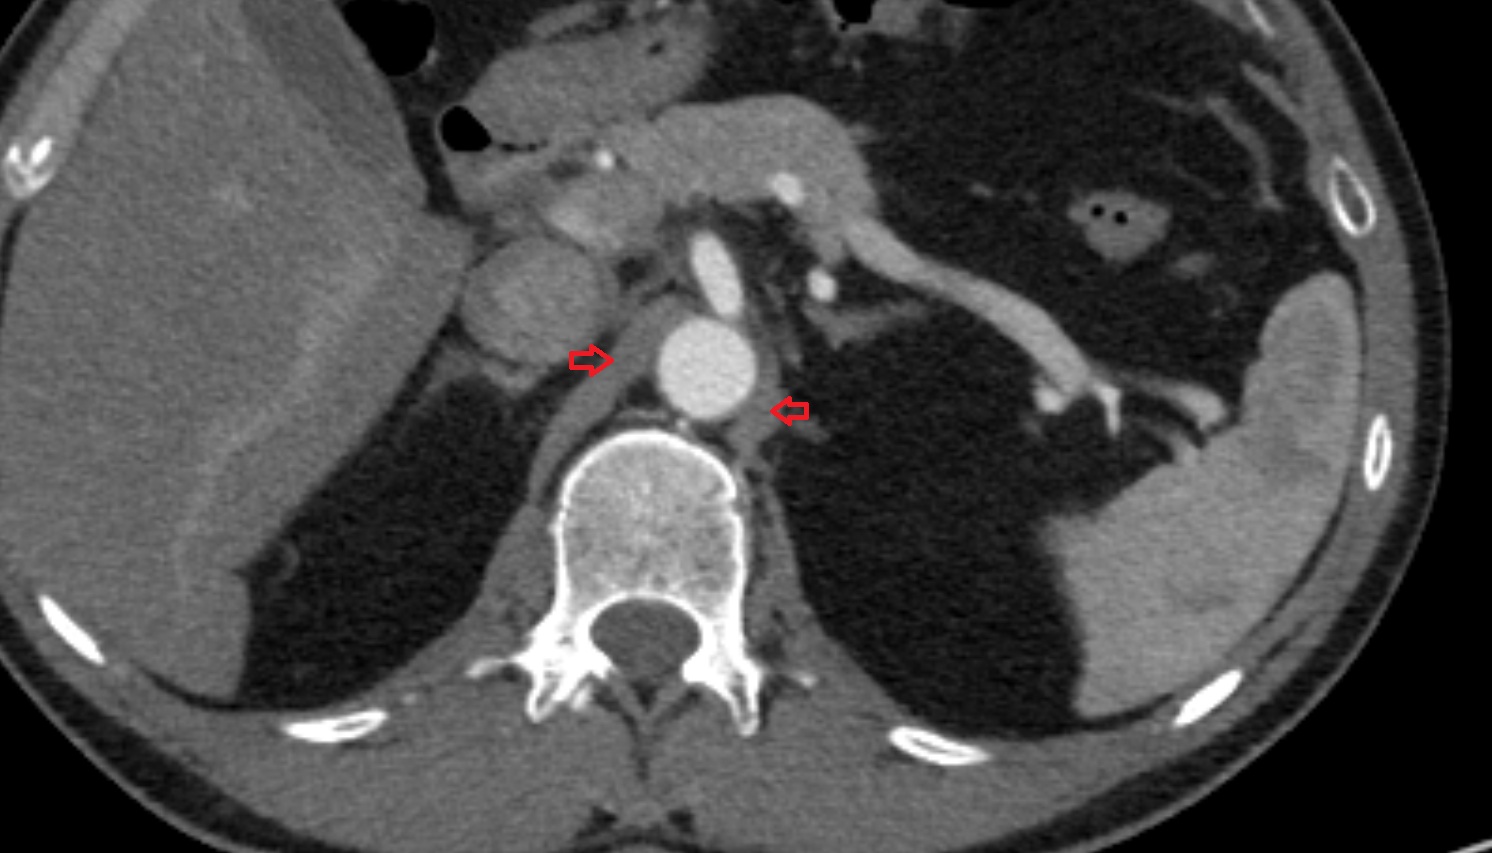

- Renal artery

- Renal vein

- Left renal vein

- Right renal vein

- Left renal artery

- Right renal artery